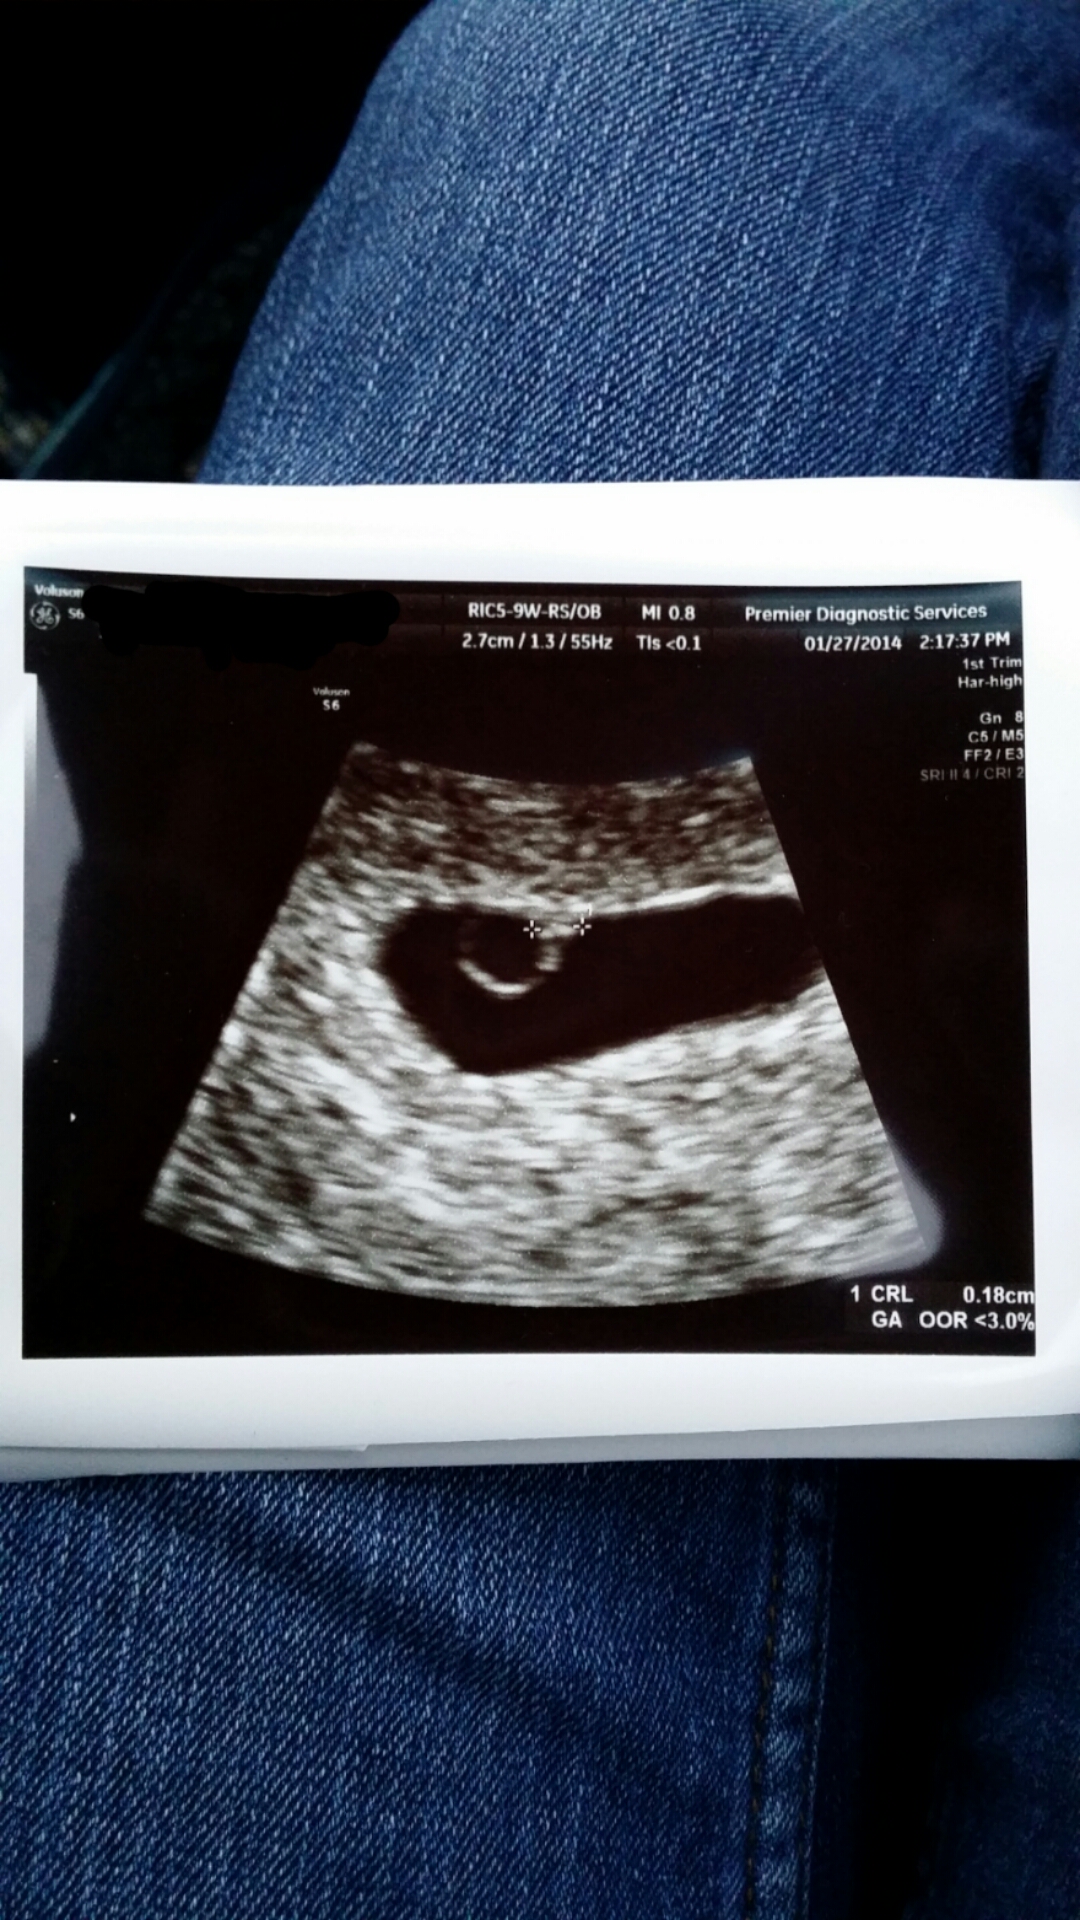

So I had my first U/S and appointment yesterday. I'm not sure why my OB office had me go in so early, but I was able to see my little bean, even though s/he is only a fetal pole with the heart flickering. I was able to see the sac and ring, and so far everything looked fine. The heartbeat was at 75 bpm, which is normal for how early she was seeing me. There was another sac that showed, but come to find out it was a tiny sac that had pooled with blood. No cause of concern at this time. Because of this, I do have another u/s next week to make sure bean is growing nicely and the heartbeat is stronger.

Here are some pictures of the party and little bean!